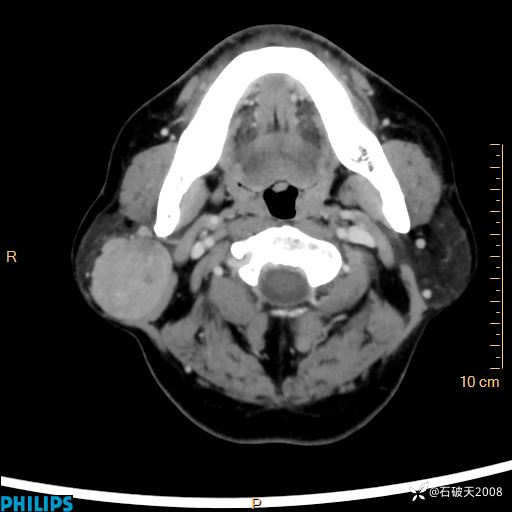

病例分享:颈部占位,一周后公布病理

男 57岁 主 诉:发现右侧颌下肿物1月余。

现病史:1月余前家属发现右侧颌下肿物。局部皮肤无红肿、热痛,无吞咽困难,无异物感,无恶心、呕吐,无头痛、头晕,无胸闷、胸痛,无发热、咳嗽、咳痰及呼吸困难。于我院行体表肿块彩超检查(2024.03.15我院)示:右侧耳下皮下软组织内低回声,未治疗。今为进一步治疗门诊以“腮腺肿瘤”为诊断收住我科,发病来患者神志清,精神可,饮食、睡眠及大小便正常,体重无明显下降。

平扫